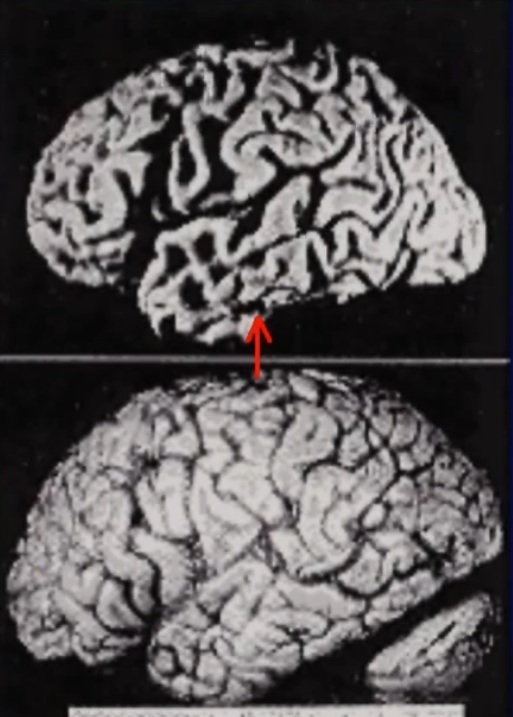

アルツハイマー型認知症は脳全体が10年以上かけてゆっくり萎縮していくため、症状も徐々に進行します。一方、脳血管性認知症は小さな脳梗塞が積み重なることで、段階的に悪化していきます。

アルツハイマー型は脳全体が均一に萎縮するため症状が予測しやすいのに対し、脳血管性は障害を受けた脳の部位によって症状が大きく異なります。

脳血管性認知症の脳

脳血管性認知症

アルツハイマー型認知症の脳

10年以上かけてゆっくりと、ほぼ予測可能な速度で進行します。脳全体が均一に萎縮していくため、症状の進行も緩やかですが確実です。